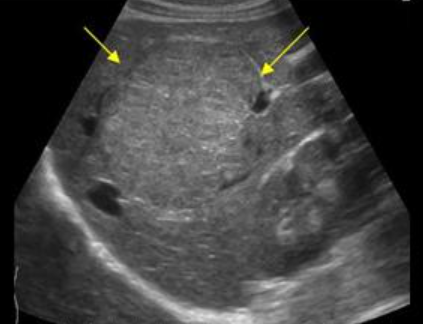

FNH의 경우 초음파소견은 다양하다. 병변은 등에코, 저에코, 고에코의 균질한 덩어리로 나타날 수 있다. 간내 혈관을 대체할 수 있는 대량 효과가 있다. 단지 18%의 사례에서만 중앙 흉터(저에코성 센터)가 존재한다. 이는 간혈관종과 매우 유사해 보인다. 또한 혈관 기형부위와 관련이 있다. 일반적으로 5cm 미만이다.

FNH (Focal Nodular hyperplasia) US finding

- spokewheel vascularity

- iso-hyperechoic mass